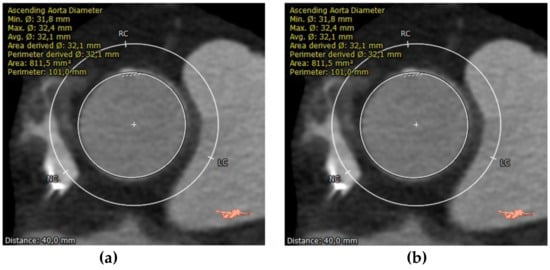

2.3.2. Aortic Annulus

The aortic annulus for implanting percutaneous prostheses is not directly visible. It is a virtual ring that passes over a plane via the basal insertions (nadir) of the aortic valve cusps. It has an oval shape that varies during the cardiac cycle, even in patients with severe calcific AS. While the size of the aortic annulus was initially determined almost exclusively via two-dimensional transesophageal echocardiography (TEE), it has been proven that the aortic annulus is a dynamic measure during the cardiac cycle. Thus, 2D imaging could not be precise enough, and only 3D imaging can display a correct measurement. Furthermore, compared with a two-dimensional assessment of the annulus, MDCT-based measures have been proven to be highly reproducible and provide a deeper understanding of annular geometry [35]. Jurenkak et al. found that, during the cardiac cycle, the aortic root varies its shape, suggesting that an MDCT evaluation during the early systole phase is the best choice for TAVI planning [36].

Annular dimension can be quantified with multiple methods: cubic spline interpolation, polygon, attenuation/Hounsfield-unit-based contour detection, and freehand contour. ECG-synchronized, ideally multiphasic, dataset should be used for proper measurement, identifying the reconstruction phase with the largest annular dimensions, thus ensuring accurate device sizing [24]. MDCT sizes the aortic annulus using annular area and perimeter measurements. In the Pivotal Trial of Medtronic Corevalve and the PARTNER 3 trial, it was demonstrated that annulus sizing based on CT measurements reduces the risk of complications such as paravalvular leakages. Moreover, the aortic annulus perimeter or cross-sectional area is superior to the annulus diameter for reducing the likelihood of paravalvular aortic regurgitation (PAR) [37,38] (Figure 3).

CT measurements of perimeter and area of aortic annulus.